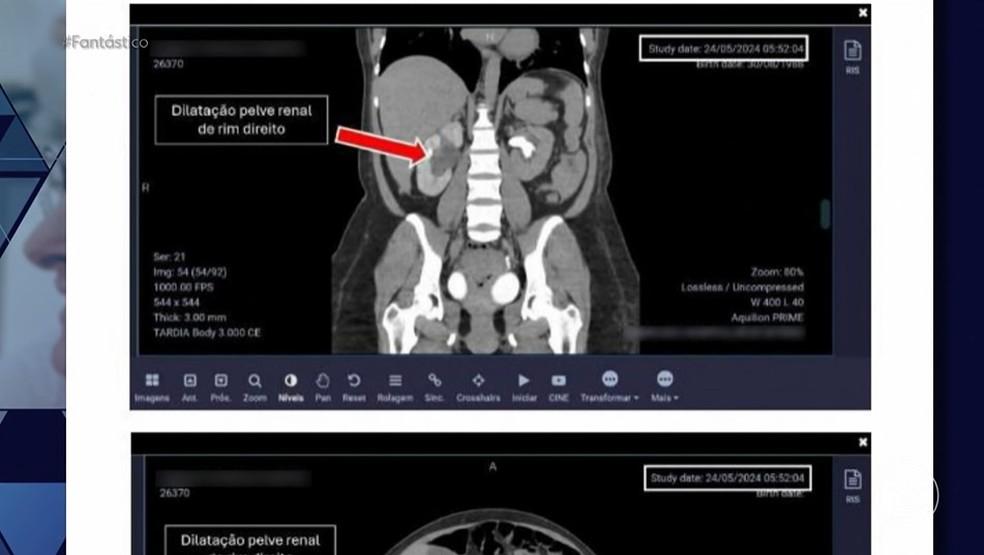

O obstetra perito Ivo Costa Júnior, que analisa um dos casos, destacou a “falta de comunicação” e os indícios de “negligência e imprudência” por parte da equipe da médica. Pacientes como Roberta Mendes também relataram sérios problemas que enfrentaram, incluindo dores persistentes e complicações médicas após cesarianas realizadas por Herief.